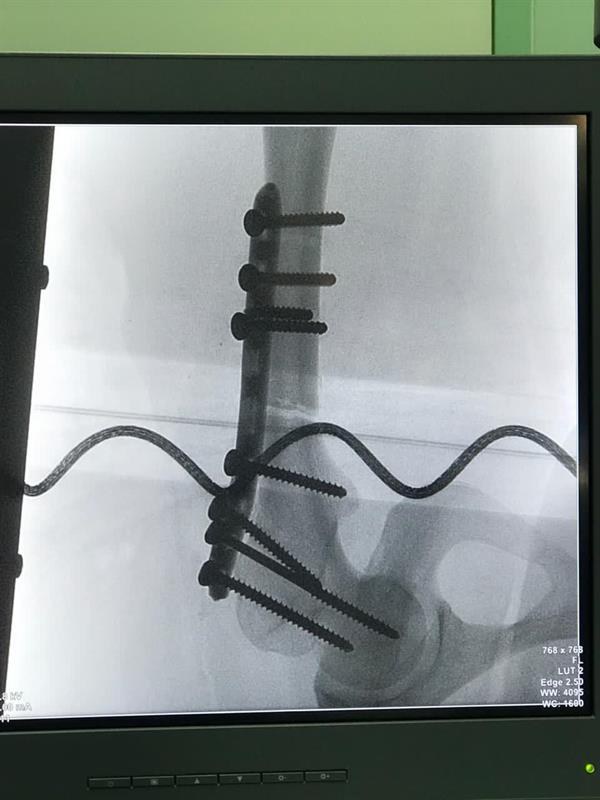

وأبان أن فريقا جراحيا بقيادة استشاري جراحة العظام الدكتور فؤاد البطاح، قام بتثبيت الكسور عند المصابين باستخدام سيخ تيتانيوم نخاعي متشابك في حالة، واستخدام شريحة تيتانيوم متشابكة في الحالة الأخرى، وذلك دون حدوث مضاعفات قبل أو بعد العملية، وتم خروج المريضين وهما يتمتعان بتلاشي الألم والتمكن من الحركة باستخدام وسائل مساعدة.